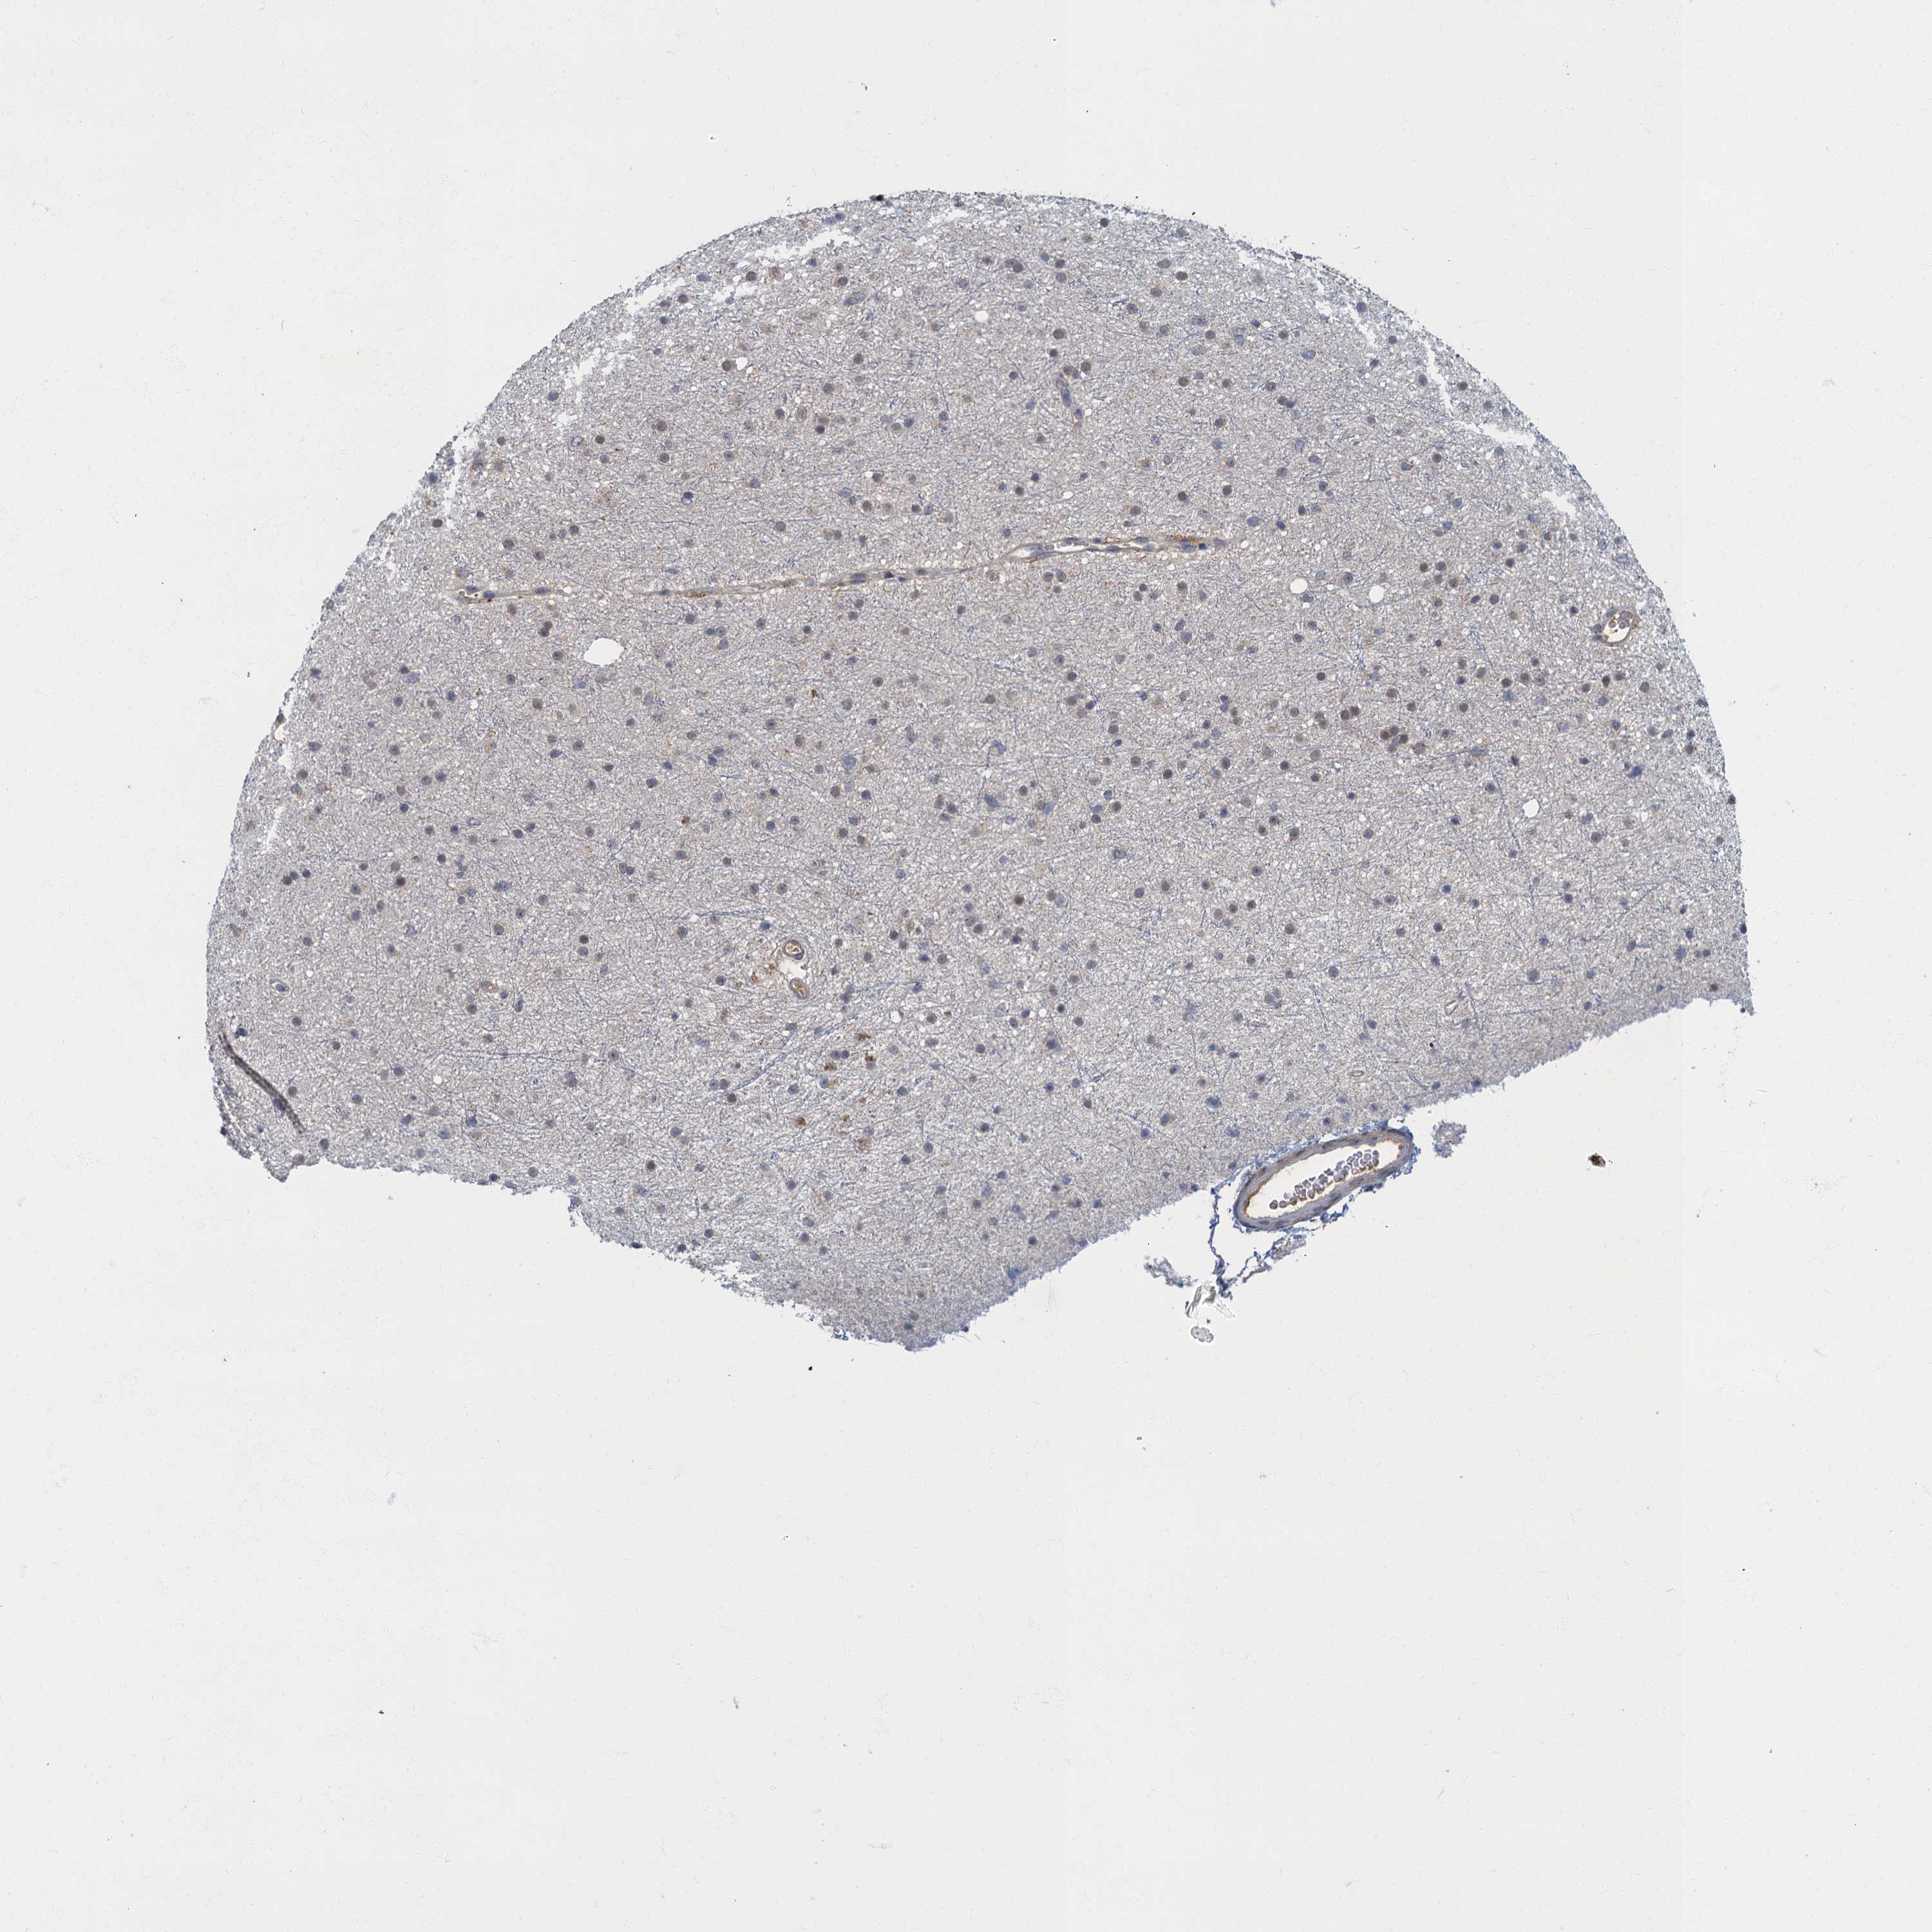

GLIOMA - Protein expressioni

A mouse-over function shows sample information and annotation data. Click on an image to view it in a full screen mode. Samples can be filtered based on level of antibody staining by selecting one or several of the following categories: high, medium, low and not detected. The assay and annotation is described here.

Note that samples used for immunohistochemistry by the Human Protein Atlas do not correspond to samples in the TCGA dataset.

Antibody stainingi

Antibody staining in the annotated cell types in the current human tissue is reported as not detected, low, medium, or high, based on conventional immunohistochemistry profiling in selected tissues. This score is based on the combination of the staining intensity and fraction of stained cells.

Each image is clickable and will lead to virtual microscopy that enables deeper exploration of all samples and also displays staining intensity scores, fraction scores and subcellular localization as well as patient and tissue information for each sample.

Antibody HPA041054

Staining

High

Medium

Low

Not detected

Intensity

Strong

Moderate

Weak

Negative

Quantity

>75%

75%-25%

<25%

None

Location

Nuclear

Cytoplasmic/membranous

Cytoplasmic/membranous,nuclear

Glioma, malignant, High grade

Glioma, malignant, Low grade